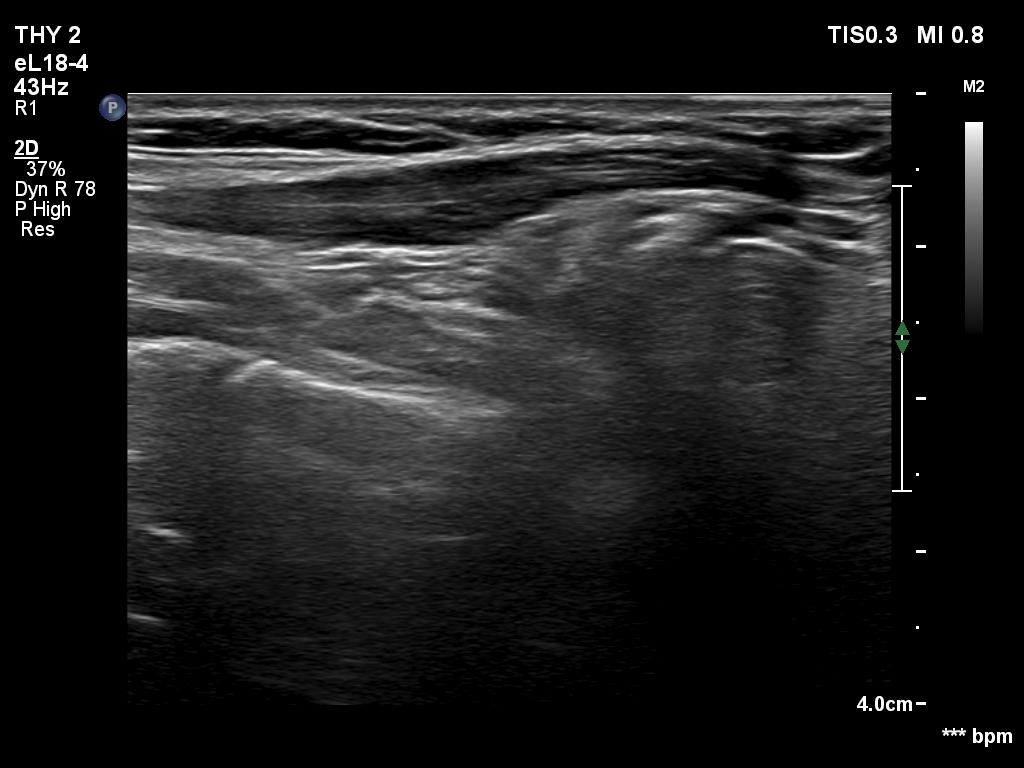

One year after surgery (second row of images):

Clinical data: The patient had no complaints.

Palpation: no abnormality.

Laboratory examination: TSH 2.05 mIU/L.

Ultrasonography. The right thyroid bed was filled with muscle fiber and connective tissue. The left lobe remained unchanged.